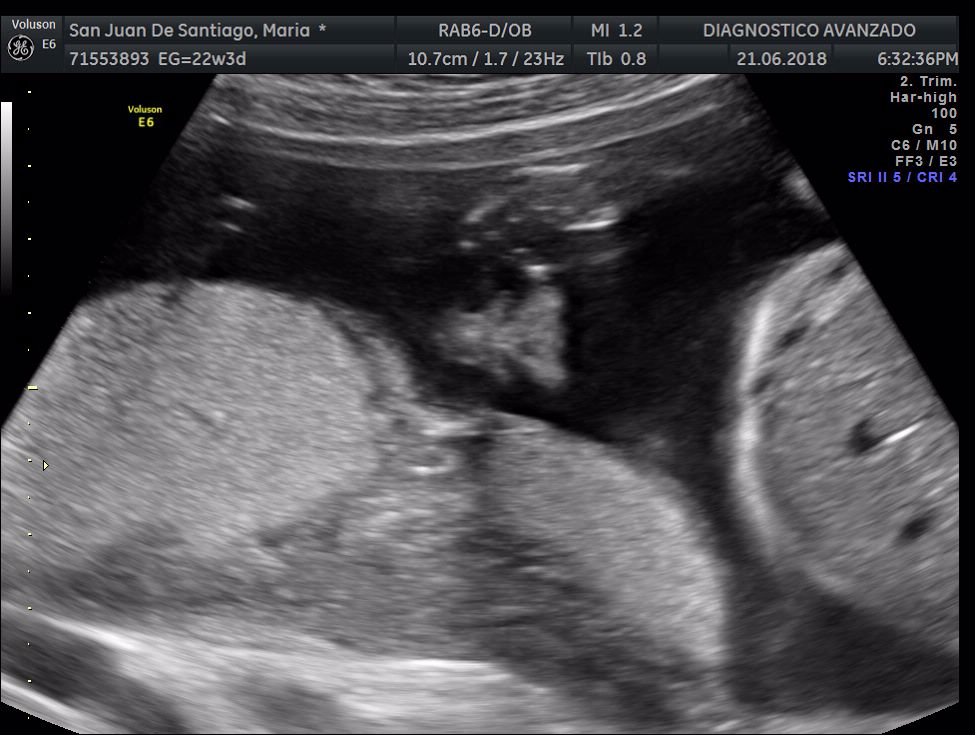

¡Hola a todos! Hoy hemos ido a hacer la tradicional ecografía 3D de la niña, os dejamos todo el material (aunque es un poco demasiado).